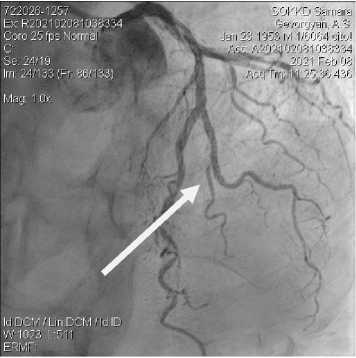

Учитывая полученные данные, принято решение о проведении МСКТ-КГ и артерий брахиоцефального ствола (БЦС) с контрастированием для верификации диагноза и определения дальнейшей тактики лечения. При контрастировании коронарных артерий и артерий БЦС выявлен гемодинамически значимый стеноз передней межжелудочковой ветви (ПМЖВ) до 75%, задней межжелудочковой ветви (ЗМЖВ) и диагональной артерии (ДА) до 90% (рис. 1), а также КТ-признаки сужения правой внутренней сонной артерии (ВСА) до 78% (рис. 2, 3).

Рисунок 1. 3D-реконструкция МСКТ-КГ. Стрелкой указаны стенозы коронарных артерий

Figure 1. 3D reconstruction of the MSCT coronary arteries. The arrow indicates coronary artery stenosis